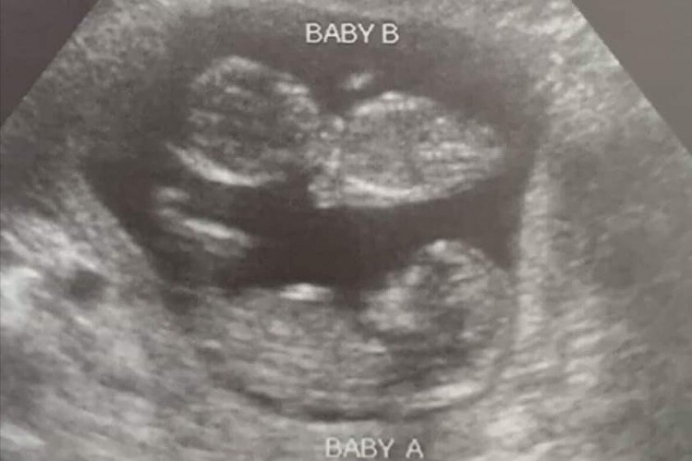

2. Twin babies survive Planned Parenthood chemical abortion

Physician Brent Boles caused a stir with a Facebook post about a pregnant patient who'd had a chemical abortion that failed, sparing her twin unborn children. Boles chronicled the patient's experience with Planned Parenthood, where she was told that the "cardiac activity" of her unborn child aged 7-8 weeks did not amount to a heartbeat. The abortion giant's staff also failed to disclose that she was having twins. Planned Parenthood had no help to offer her after she had returned there and learned she was still pregnant after the failed chemical abortion. This mother was connected with Boles through the Abortion Pill Rescue Network. It was determined that the Abortion Pill Reversal protocol of extra progesterone was not necessary in this particular case. Boles proceeded to dissect Planned Parenthood's handling of the case on Facebook.